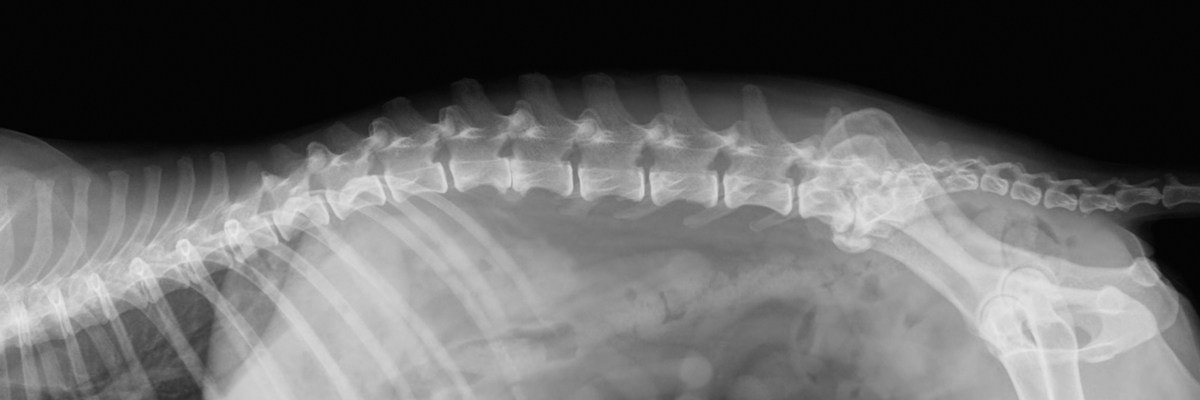

Essentiell ist die Röntgenuntersuchung in der Kleintiermedizin in vielen Bereichen der Skelett- und Weichteildiagnostik. Frakturen und Luxationen, degenerative Gelenkveränderungen, genetisch bedingte angeborene Skelettanomalien können gleichsam wie bestimmte Veränderungen an inneren Organen, Tumore, Flüssigkeitsansammlungen in den Körperhöhlen, Fremdkörper etc. nur durch röntgenologische Abklärung eindeutig erkannt und somit auch bestehende Therapiemöglichkeiten genauer abgeklärt werden.